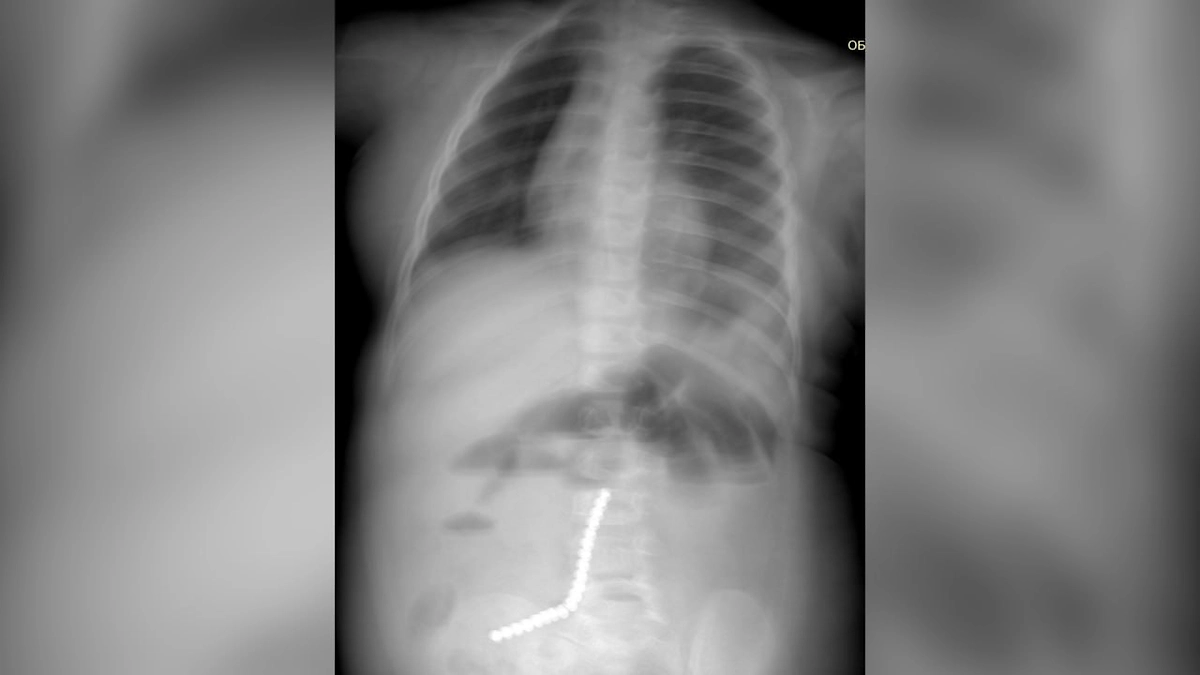

Малыш поступил в начале февраля с рвотой и резким ухудшением состояния. Рентген показал наличие 20 инородных тел в желудочно-кишечном тракте. Девять магнитов удалось извлечь эндоскопом, но остальные успели мигрировать в кишечник, вызвав перфорацию.

«Петли тонкой, сигмовидной и слепой кишки слиплись между собой из-за магнитного притяжения», — прокомментировал хирург Булат Шагдаров.

Потребовалась открытая операция. Медики удалили часть тонкой кишки с прободением, ушили свищи, а также аппендикс, куда попала часть магнитов. Сейчас ребёнок переведён из реанимации и продолжает лечение под наблюдением врачей.